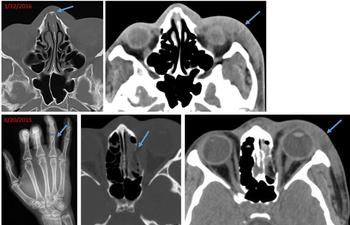

Images that show specific types of injuries and old injuries could help radiologists identify victims of domestic and sexual abuse.